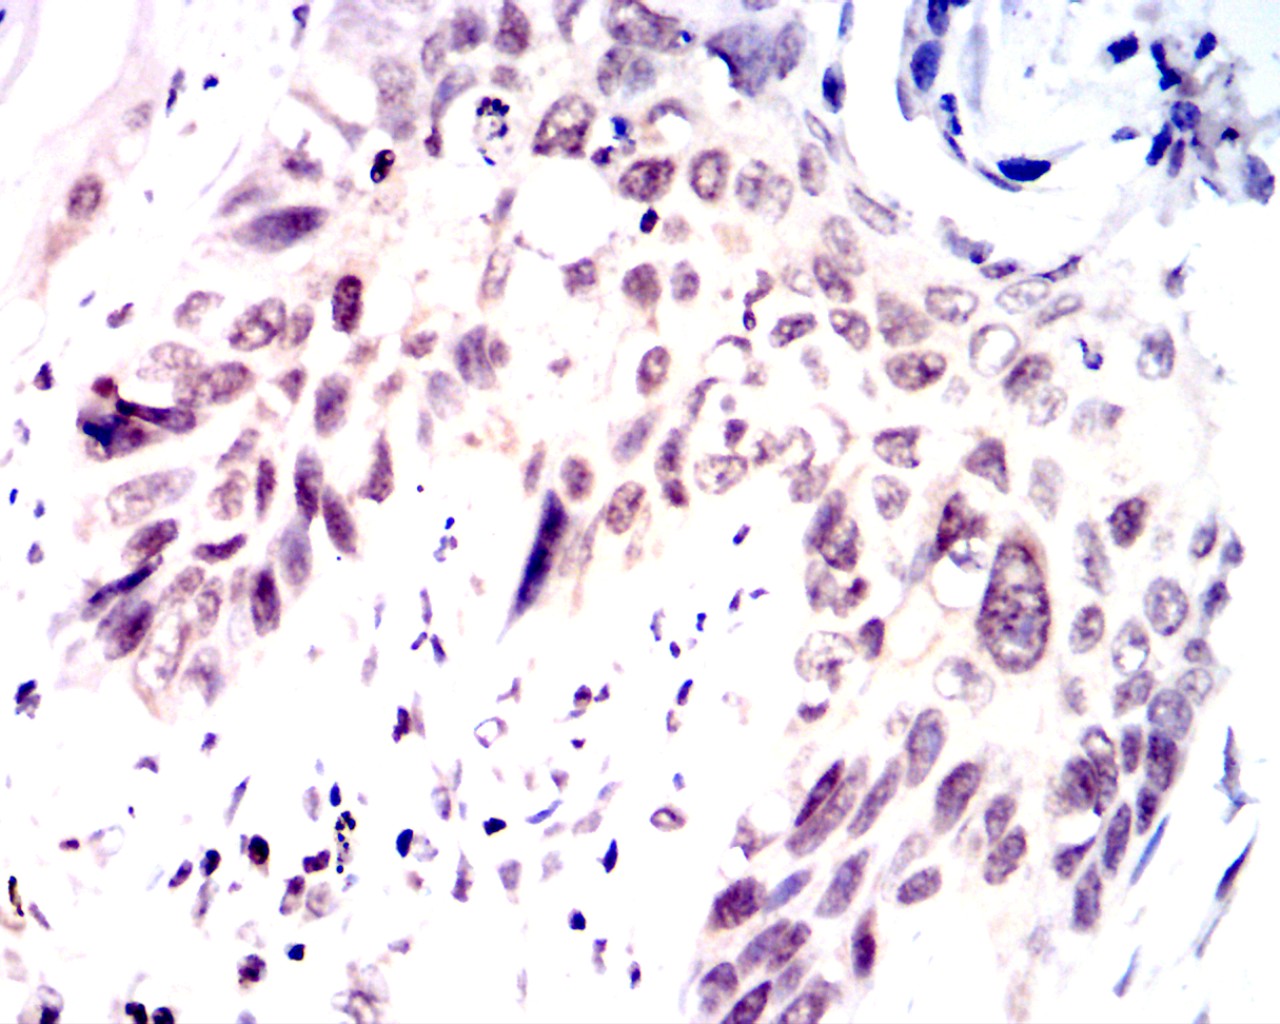

Immunohistochemical analysis of paraffin-embedded rectal cancer tissues using LSD1 antibody with DAB staining.Pre-treat the sections with heat-mediated antigen retrieval using sodium citrate buffer (pH 6.0) (OM750020) for 2 minutes. Wash the sections with ddH₂O and PBS (OM750003). Block the tissue with 10% non-immune goat serum(OM760028) at room temperature for 30 minutes. Incubate the tissue with the primary antibody diluted at a ratio of 1:1500 at 4°C overnight. At room temperature, dilute the secondary antibody, Goat Anti-Mouse IgG (H&L) - HRP(OM644366), at a ratio of 1:200 and incubate for one hour. Use DAB(OM760029)as the chromogenic agent. Counterstain the tissue with hematoxylin, and mount the tissue sections with neutral gum.WB

Immunohistochemical analysis of paraffin-embedded rectal cancer tissues using LSD1 antibody with DAB staining.Pre-treat the sections with heat-mediated antigen retrieval using sodium citrate buffer (pH 6.0) (OM750020) for 2 minutes. Wash the sections with ddH₂O and PBS (OM750003). Block the tissue with 10% non-immune goat serum(OM760028) at room temperature for 30 minutes. Incubate the tissue with the primary antibody diluted at a ratio of 1:1500 at 4°C overnight. At room temperature, dilute the secondary antibody, Goat Anti-Mouse IgG (H&L) - HRP(OM644366), at a ratio of 1:200 and incubate for one hour. Use DAB(OM760029)as the chromogenic agent. Counterstain the tissue with hematoxylin, and mount the tissue sections with neutral gum.